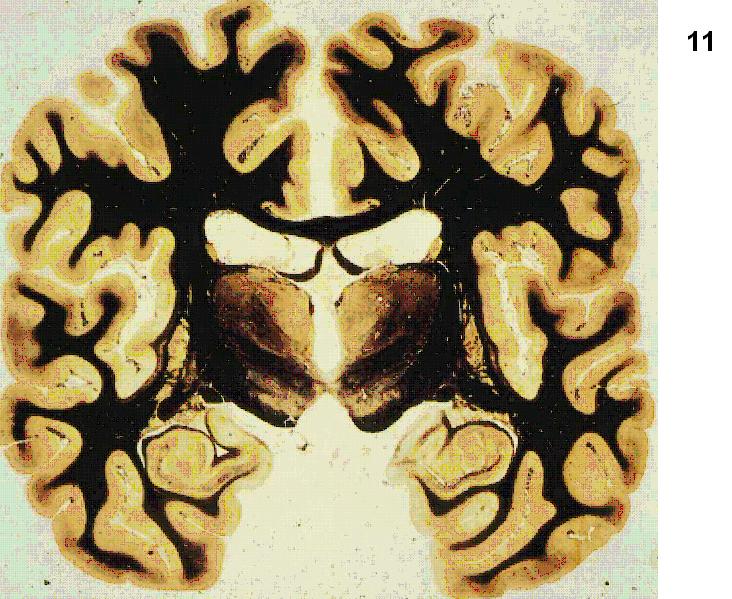

Figure 4 Figure 5 Figure 6 Figure 7 Figure 8 Figure 9 Figure 10 Figure 11